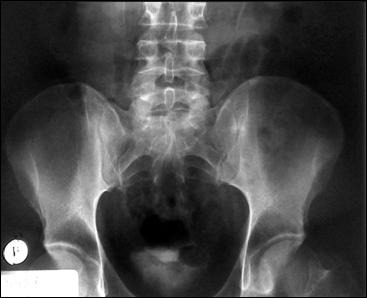

4.1. Radiografia renovezicala simpla si UIV raman examenele de baza pentru diagnosticul etiologic al oricarui pacient cu hematurie. Tumorile vezicale au drept semn radiologic cardinal imaginea lacunara pe cistograma urografica. Tumorile infiltrative pot induce modificari ale supletii peretelui vezical, care devine rigid, inextensibil, retractat etc. in zonele patologice. Ureterohidronefroza sau rinichiul mut sunt rezultatele invaziei si obstructiei ureterelor intramurale induse de tumorile solide, infiltrative (Fig.27,28,29).

Figura 28. Imagine

lacunara de 2,8/2 cm, in aria vezicii urinare, sugerand tumora

vezicala.